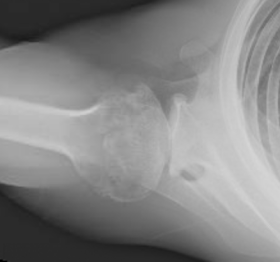

At a recent Cantina luncheon, conversation among five shoulder surgeons concluded that shoulder surgeons are becoming divided with respect to their approaches to arthritic shoulders with glenoid retroversion: there are the "acceptors" and the "correctors".

The acceptors ream the glenoid only enough to create a smooth concavity that corresponds to the backside of the glenoid component. The correctors strive to reduce glenoid retroversion to 15 degrees or less, using posteriorly augmented glenoid components, anterior "high side" reaming, or posterior bone graft.

The acceptor approach requires only standardized plain radiographs and the occasional use of anteriorly eccentric humeral head components and rotator interval plication if excessive posterior decentering is noted at surgery.

By contrast, the corrector approach usually requires a preoperative CT scan, three dimensional planning, and some means of carrying out the plan in the operating room, such as patient specific instrumentation or computer guidance.